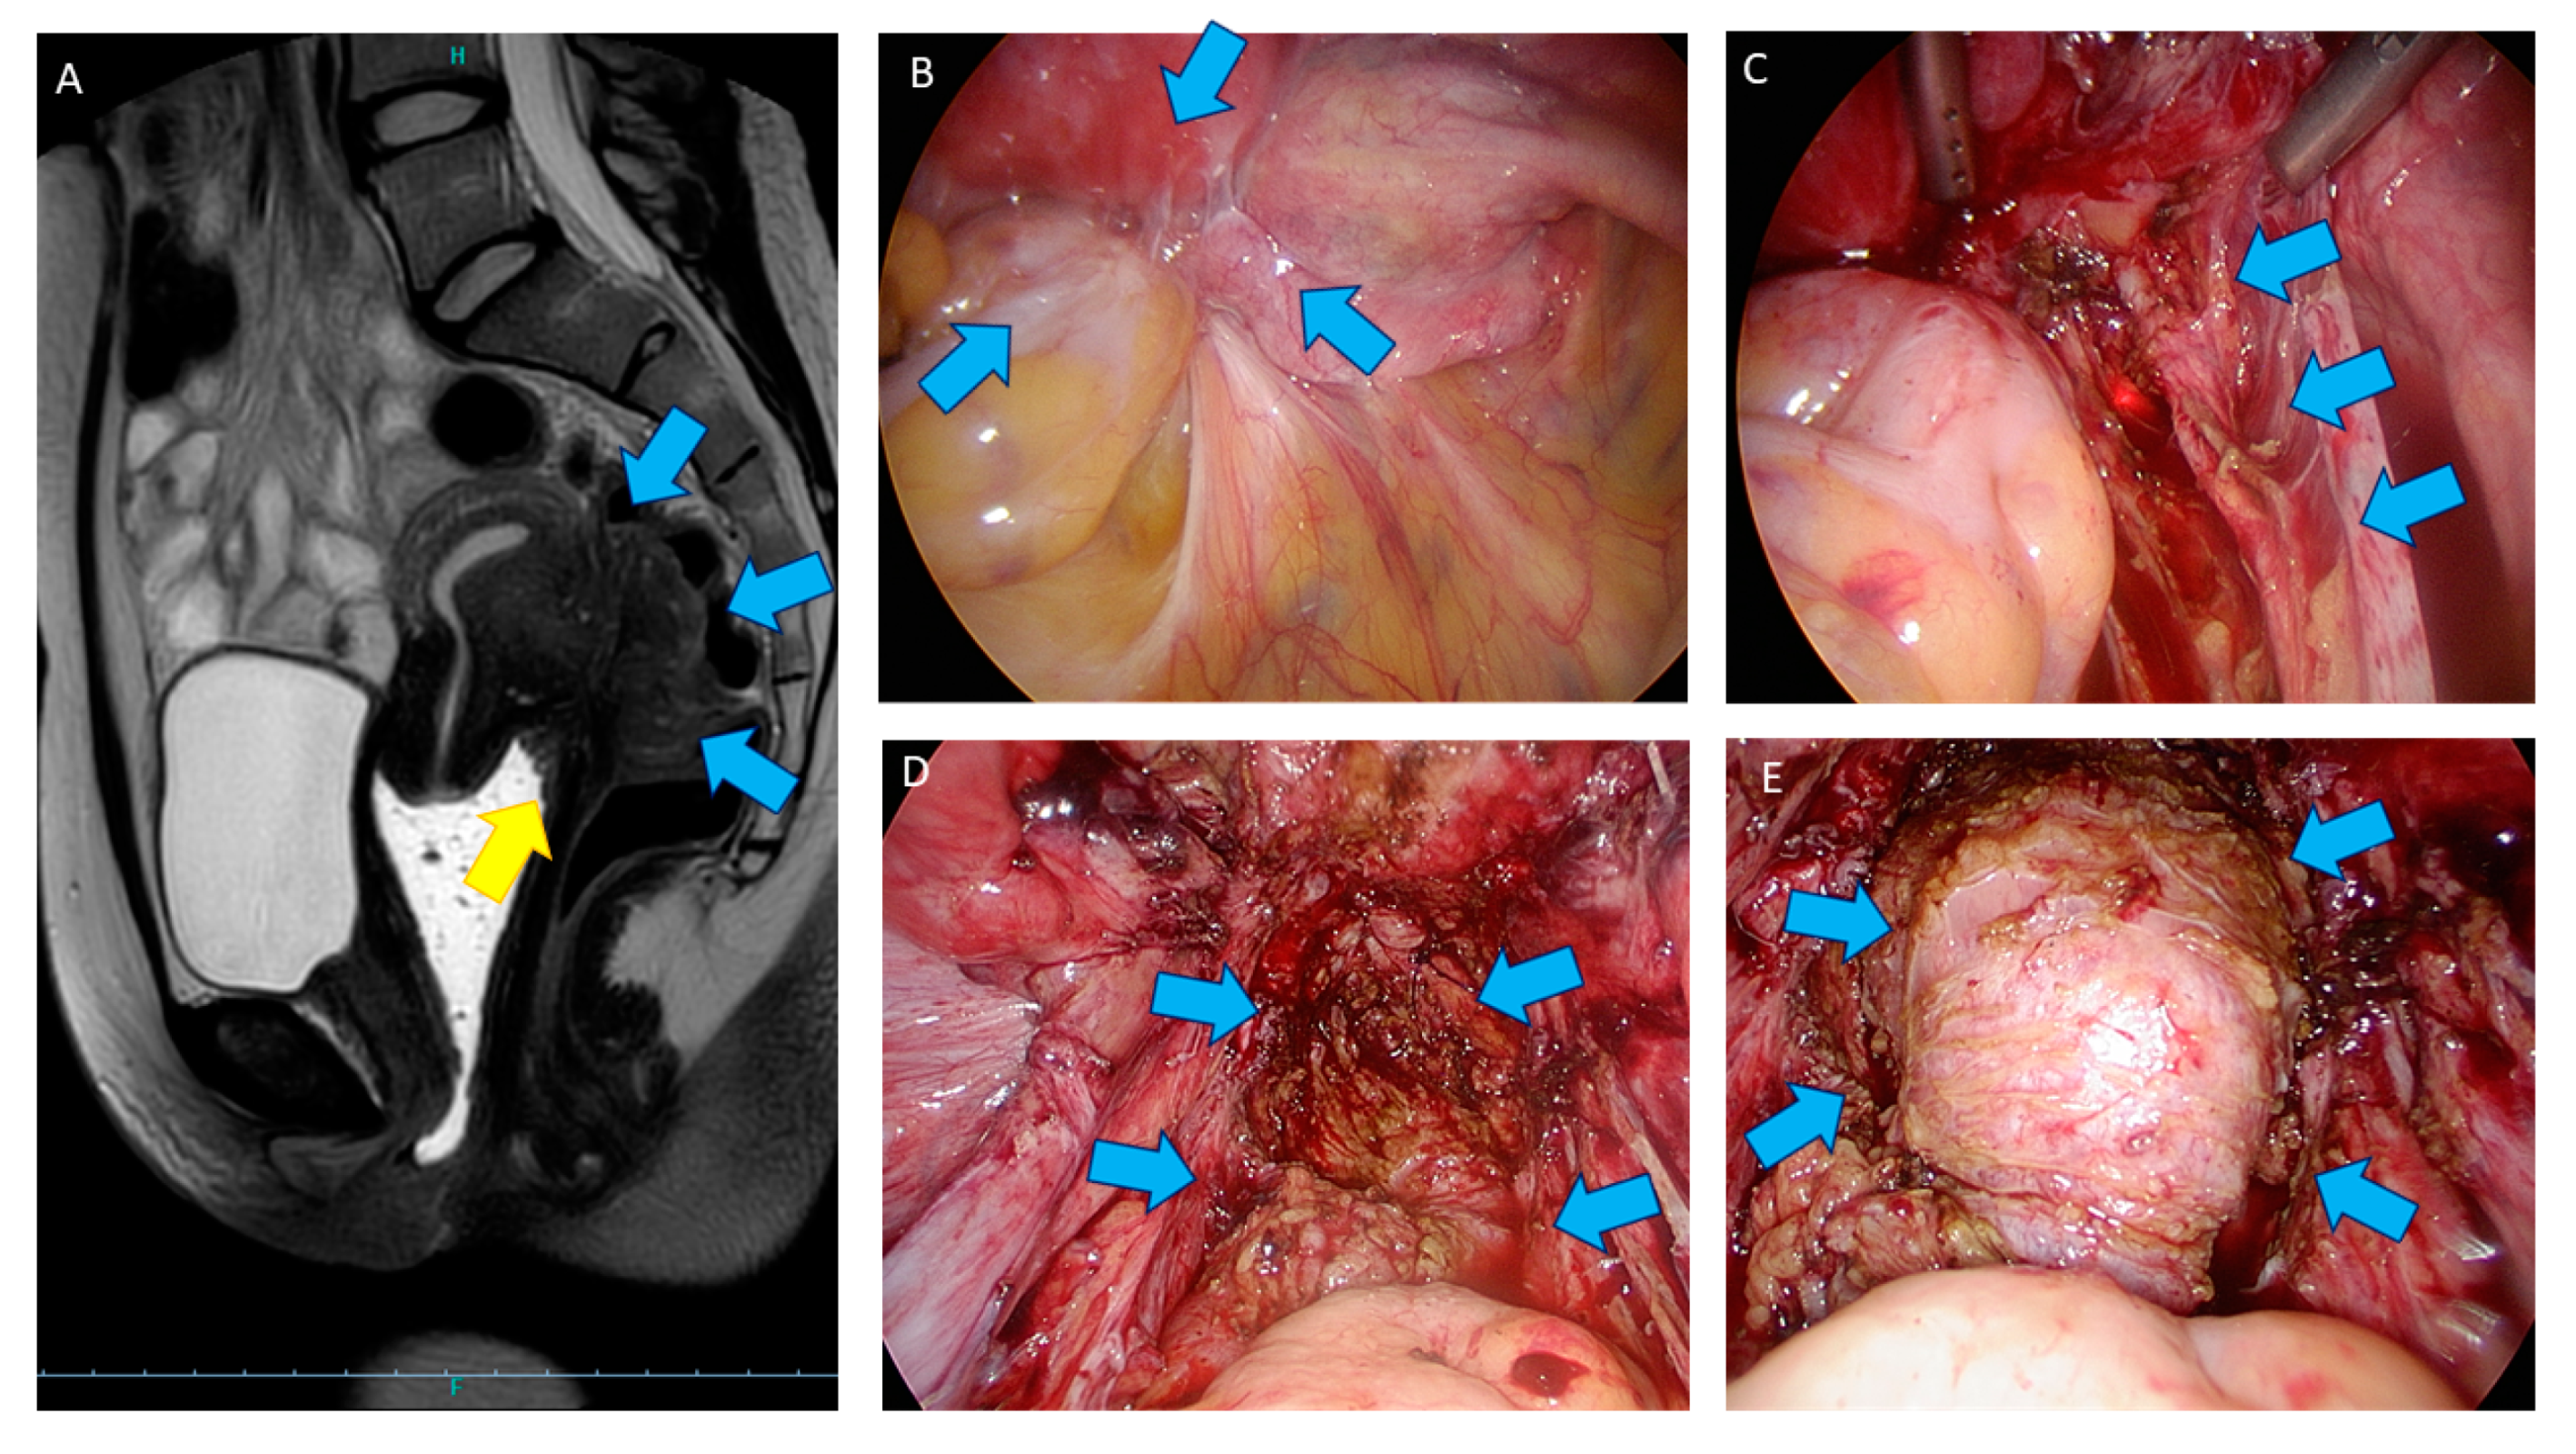

- Bazot, M.; Bharwani, N.; Huchon, C.; Kinkel, K.; Cunha, T.M.; Guerra, A.; Manganaro, L.; Buñesch, L.; Kido, A.; Togashi, K.; et al. European society of urogenital radiology (ESUR) guidelines: MR imaging of pelvic endometriosis. Eur. Radiol. 2017, 27, 2765–2775. [Google Scholar] [CrossRef]

- Jaramillo-Cardoso, A.; Shenoy-Bhangle, A.S.; VanBuren, W.M.; Schiappacasse, G.; Menias, C.O.; Mortele, K.J. Imaging of gastrointestinal endometriosis: What the radiologist should know. Abdom. Radiol. 2020, 45, 1694–1710. [Google Scholar] [CrossRef]

- Bazot, M.; Kermarrec, E.; Bendifallah, S.; Daraï, E. MRI of intestinal endometriosis. Best Pract. Res. Clin. Obstet. Gynaecol. 2021, 71, 51–63. [Google Scholar] [CrossRef] [PubMed]

4. Shaving Technique: Surgical Procedure

4.2. Surgical Technique